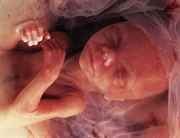

С этого момента развитие зародыша человека по неделям беременности превращается в развитие ребенка по неделям беременности, так как в животе у будущей мамы уже функционирует полноценный организм, со всеми сформировавшимися внутренними и внешними органами.

Полностью сформированы органы дыхания, пищеварительная, нервная и кровеносная системы. На 17-20 неделе на всём теле малыша за исключением лица формируется слой подкожного жира.

Личико очень морщинистое, на голове растут волосики. На пальчиках малыша начинают расти ногти, появляется сосательный рефлекс. Замедляется рост головки, и она уже составляет треть длины тела. Рост малыша к концу пятого месяц составляет примерно 25 см, а весит он 300-400 грамм.

К этому времени мама прибавляет в весе около 4 кг.